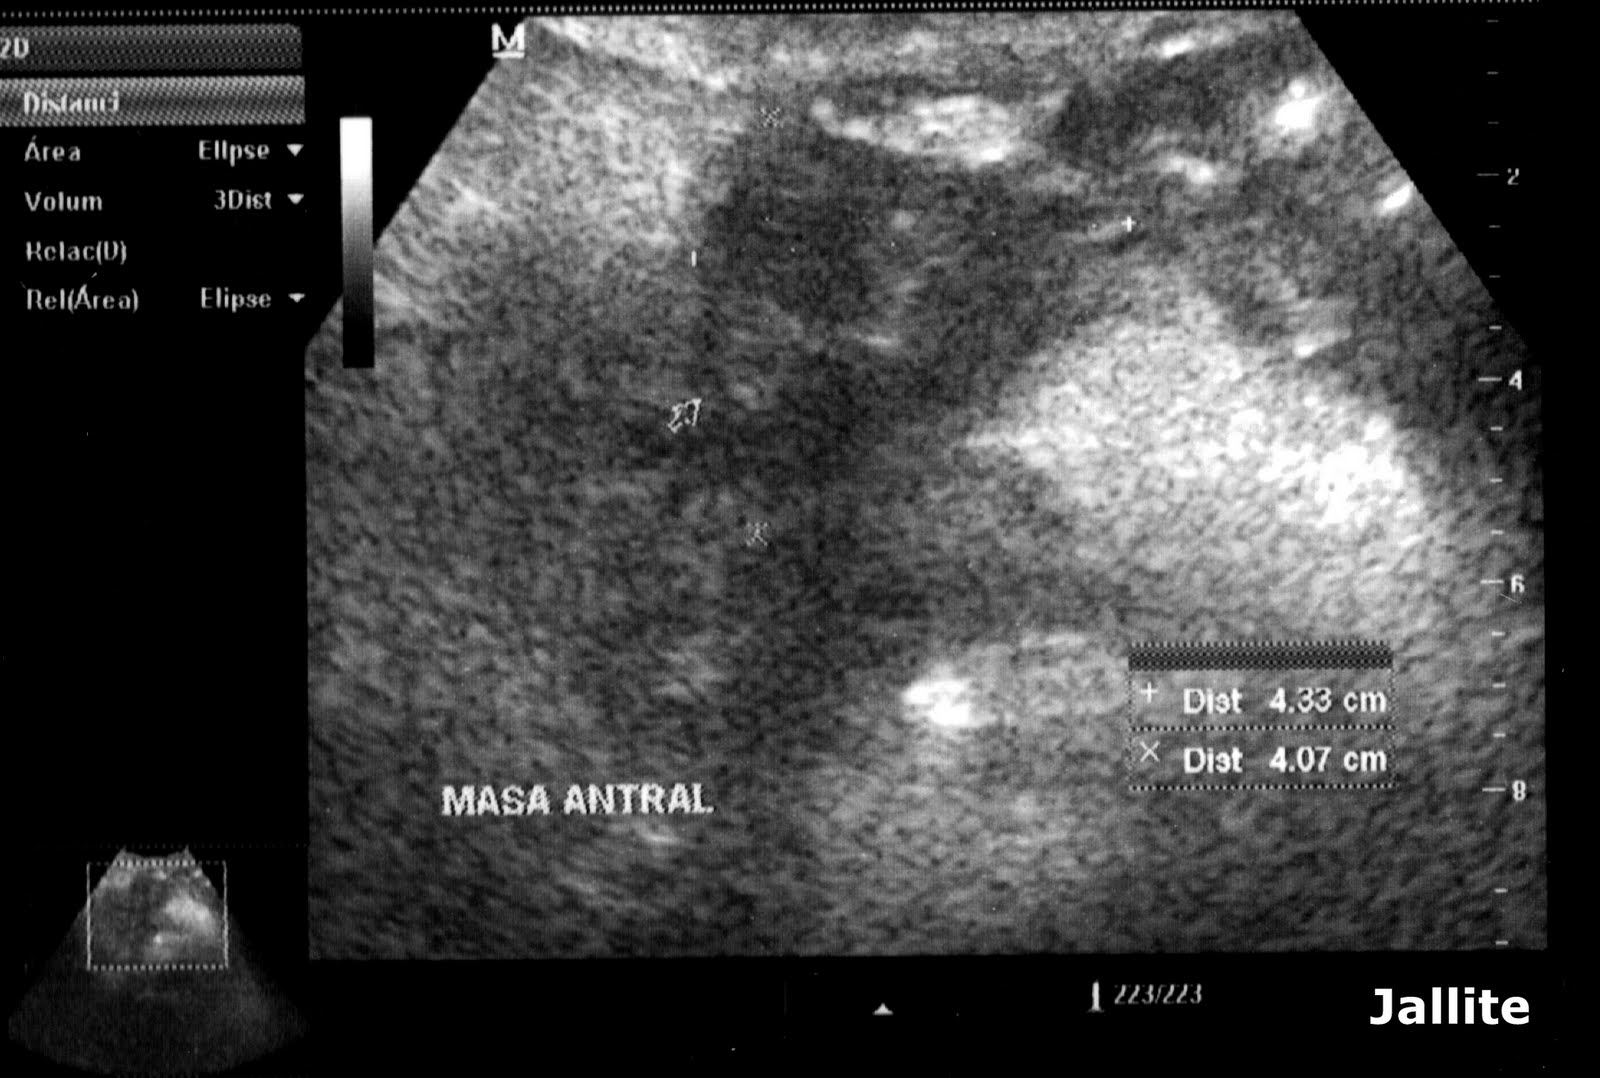

From www.elsevier.es

Quiste de duplicación entérica como presentación poco frecuente de Que Es Un Quiste En El Estomago Algunos quistes pequeños no causan síntomas; Te explicamos por qué salen los quistes en el páncreas, cuándo necesitan tratamiento y qué remedios caseros pueden ayudarte a mejorar la salud de este órgano. ¿qué es un quiste pancreático? Conoce más sobre los síntomas,. Un quiste es un crecimiento excesivo del epitelio, células especializadas que residen en la superficie del tejido, como. Que Es Un Quiste En El Estomago.